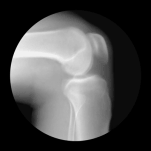

据了解,吴京的膝盖早在2017年拍摄完《战狼2》后就出现了骨关节炎。因为拍摄武打动作吴京经常受伤,而且还是重复性受伤。之前手术的影像资料显示,吴京的软骨组织已经碎到完全烂掉,像海底的海草一样。

骨关节炎,又称退化性关节炎,是关节炎的一种类型。因为平时膝关节负重最大,活动最多,致残的几率比较高。据不完全统计,目前世界上骨关节炎造成的软骨损伤病人约有3亿。

值得注意的是,骨关节炎中的“炎症”并不是我们平常所认为的“发炎了”,而是一种关节老化、蜕变、磨损加重而引起的病理现象,以关节疼痛、肿胀、畸形、僵硬症状为主,后期还会导致关节功能丧失而致残,素有“致残杀手”之称。

童培建主任说,目前骨关节炎传统治疗方法效果有限,置换关节面临着异体排斥、后遗症多等问题。“干细胞治疗方法”就应运而生,主要是用于修复损伤的软骨、OCD软骨软化症、骨头坏死及骨质不愈合。目前在日本、韩国已正式公开应用,在我国还在临床试验阶段。据悉,吴京在2017年就曾前往日本进行干细胞靶向治疗骨关节炎。